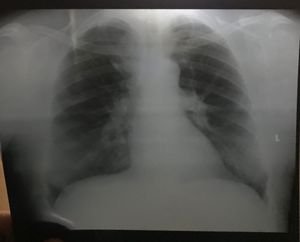

Whatโ€™s your diagnosis

I think hilar......๐Ÿ˜•๐Ÿ˜•๐Ÿ˜•

Consolidation .. Pneumonia Of Lower Lobe Of Right Lung ?

Bilateral hilar lymphadenopathy with ARDS